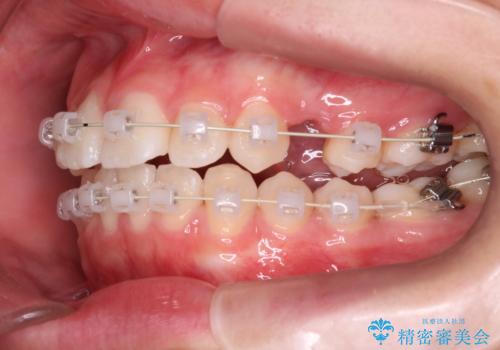

- 矯正装置

- 審美装置

- 治療期間

- 2年3ヶ月

抜歯をしてワイヤー矯正を行いました。

上顎両側小臼歯を抜歯して治療を行い、突出感も大幅に改善しました。